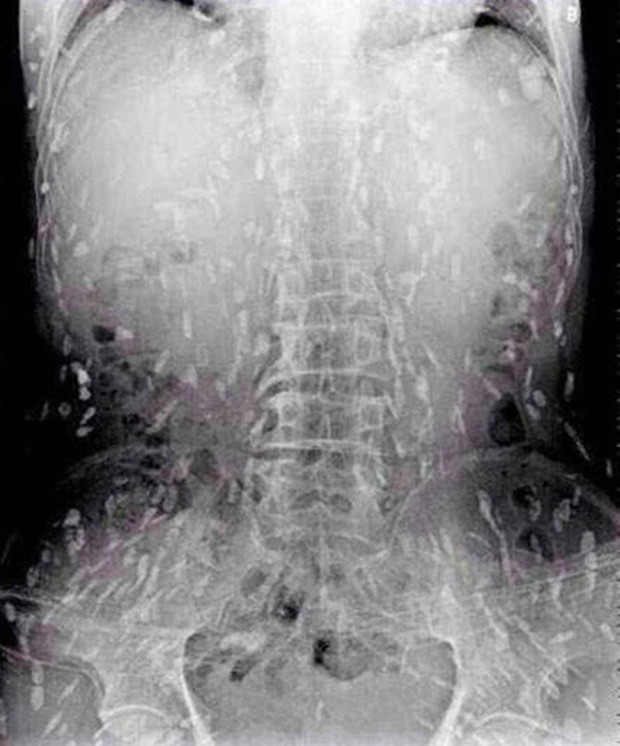

Theo tờ Epochtimes, vào khoảng tháng 9/2014, một người đàn ông sống tại tỉnh Quảng Đông (Trung Quốc) đã nhập viện điều trị trong tình trạng đau bụng dữ dội. Qua kiểm tra, các bác sĩ Bệnh viện liên kết thứ 5 tỉnh Quảng Đông đã rất bất ngờ khi phát hiện thấy sán làm tổ khắp cơ thể anh. Người đàn ông cho biết, sashimi là món ăn mà anh yêu thích, vì vậy 14 ngày trước đó, anh ta ăn rất nhiều cá sống. Ngoài những cơn đau bụng dữ dội, người đàn ông này còn có triệu chứng bị mẩn ngứa da.

| Sán làm tổ khắp cơ thể người đàn ông. |

Tuy nhiên, do bệnh tình đã bước sang giai đoạn nghiêm trọng nên người đàn ông tiếp tục được chuyển tới Bệnh viện Nhân dân số 8 ở Quảng Châu để điều trị. Kết quả chụp X-quang cho thấy, những đốm trắng nhỏ xuất hiện lấm chấm khắp cơ thể chính là sán.